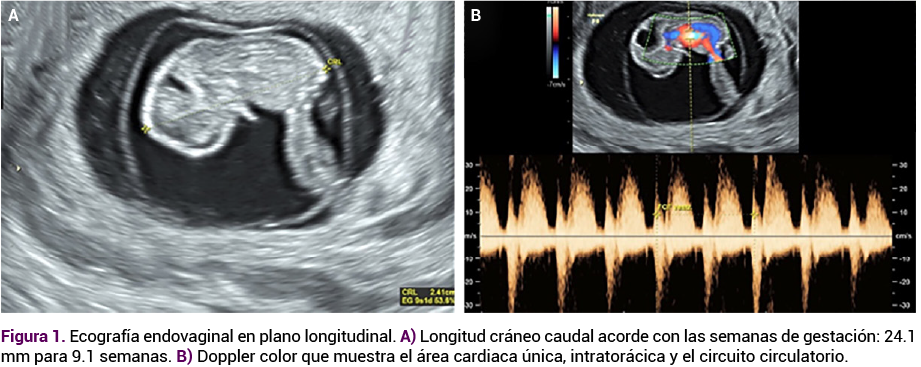

La reacción corial era adecuada, sin desprendimientos ni hematomas, con cuello uterino cerrado. Impresión diagnóstica: embarazo de 9.1 semanas con malformación grave en el espacio craneofacial de aspecto bífido, compatible con diprosopia, y anomalías en la fosa posterior de aspecto quístico (Figura 2 A-D).

<strong>Figura 2</strong>

Figura 2. Hallazgos craneofaciales de aspecto bífido compatibles con duplicación facial, con cambios quísticos en fosa posterior (vistas A a D).